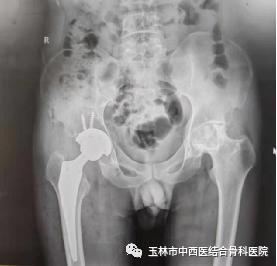

图一为患者术前DR结果

图二为患者髋关节置换术后DR结果

36岁的卢先生来到玉林市中西医结合骨科医院,入住髋关节一科,经该科黎观保主任和刘桐源医生询问病史、查体、阅片后诊断为“双侧股骨头坏死”,为卢先生制定了“直接前方入路(DAA)人工全髋关节置换术”的治疗方案。

手术当日,髋关节一科黎观保主任带领团队在麻醉科、手术室的配合下为卢先生进行了直接前路(DAA)微创人工右髋关节置换手术。由于手术创伤小,术中几乎没有出血,对肌肉组织损伤也非常轻微,麻醉苏醒后的卢先生便可立即自主活动髋关节,能够轻松抬腿了,而且自觉没有明显疼痛感。